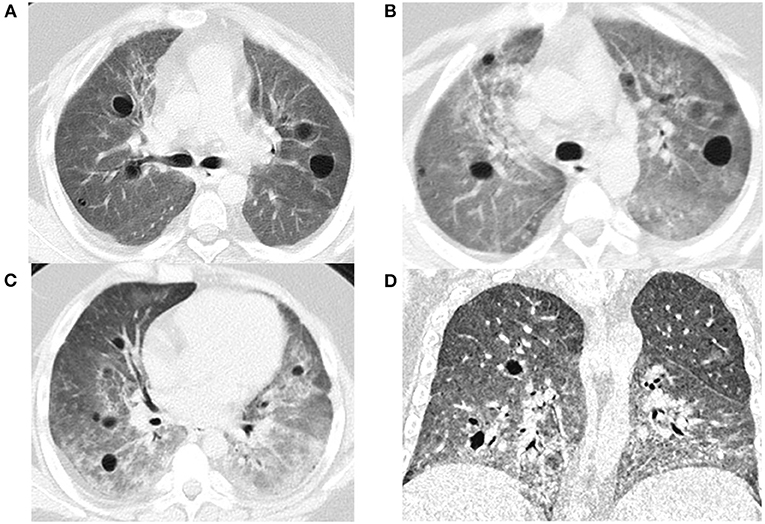

Se trata de una enfermedad que genera una inmunodeficiencia primaria que se caracteriza por una desregulación inmunitaria con autoinflamación y autoinmunidad. La causa genética de la misma es un trastorno autosómico dominante causado por mutaciones en el gen que afecta el transporte de proteínas dentro de las células. Los pacientes desarrollan autoanticuerpos y una respuesta inmune desregulada, que puede incluir un aumento en la producción de interferones tipo 1. Y los síntomas que produce el síndrome dolores corporales severos producto de afecciones pulmonares, renales y articulares.